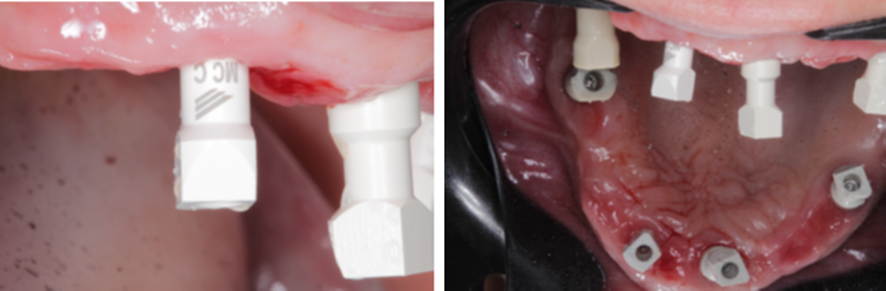

Optamos então por substituir o componente protético do elemento 12, de Mini Cônico 4,8 mm de diâmetro e 2,5 mm de cinta gengival, para Micro Cônico 3,5 mm de diâmetro e 1,5 mm de cinta gengival.

Feito novo escaneamento de transferência.

Instalação da prótese em PMMA.